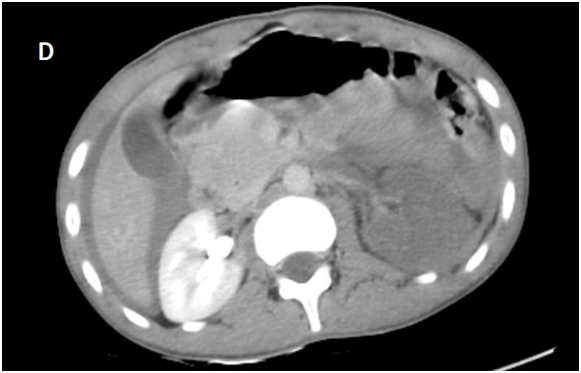

Whole body CT Scanner was performed 5hours after the accident Figure 1, which revealed a laceration fracture of the spleen responsible for a low abundant intraperitoneal hematoma, associated with left renal ischemia due to a sub intimal damage on the left renal artery wall, with formation of a secondary obstructive thrombus, in addition to a left peri-renal hematoma of 16mm, without parenchymal lesions or extravasation of contrast, otherwise ; left vein, the right kidney and his pedicle were intact.

Figure 1A Contrast enhanced CT abdominal scan.

Figure 1B Contrast enhanced CT abdominal scan.

Figure 1C Contrast enhanced CT abdominal scan.

Figure 1D Late acquisition of contrast enhanced CT abdominal scan.

laceration fracture of the spleen responsible for a low abundant intraperitoneal hematoma, associated with left renal ischemia due to a sub intimal damage on the left renal artery wall, with formation of a secondary obstructive thrombus, in addition to a left peri-renal hematoma of 16mm, without parenchymal lesions or extravasation of contrast, otherwise ; left vein, the right kidney and his pedicle were intact.

A Contrast enhanced computed tomography control was performed at D+7 showing a sudden stop of the Contrast progression at the initial portion of the left renal artery, leading to total left renal ischemia, with stability of the perirenal hematoma, spleen injury and no extravasation at the late acquisitions.